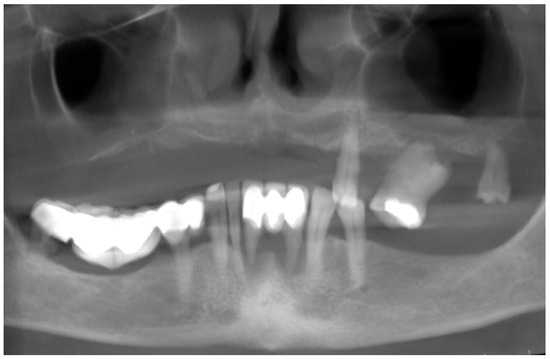

2. Patient Information and Clinical Findings